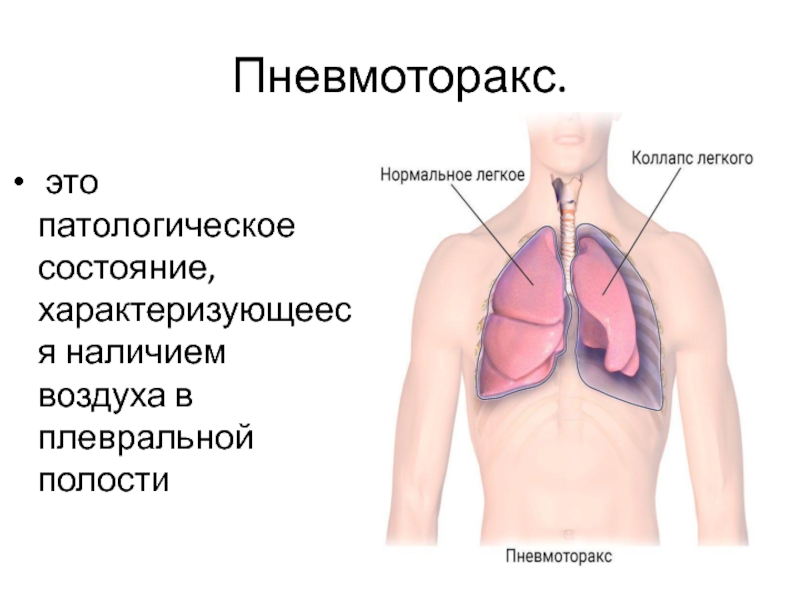

Схемы дыхания: Пневмоторакс на изображениях